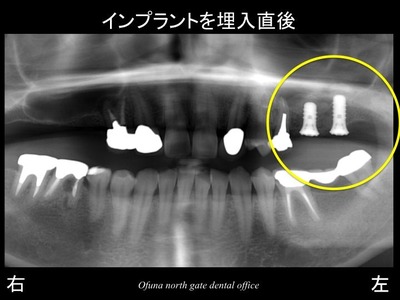

ソケットリフト法を応用してインプラント治療を行う治療計画を立てました。

この拡大レントゲンに先程の骨のラインと上顎洞の線を記入してみます。

さらにこのレントゲン写真にソケットリフト法を行った後の上顎洞を書いてみます。

青線が挙上された上顎洞の位置です。

挙上された上顎洞の内部には人工の骨(βーTCP)が入っています。